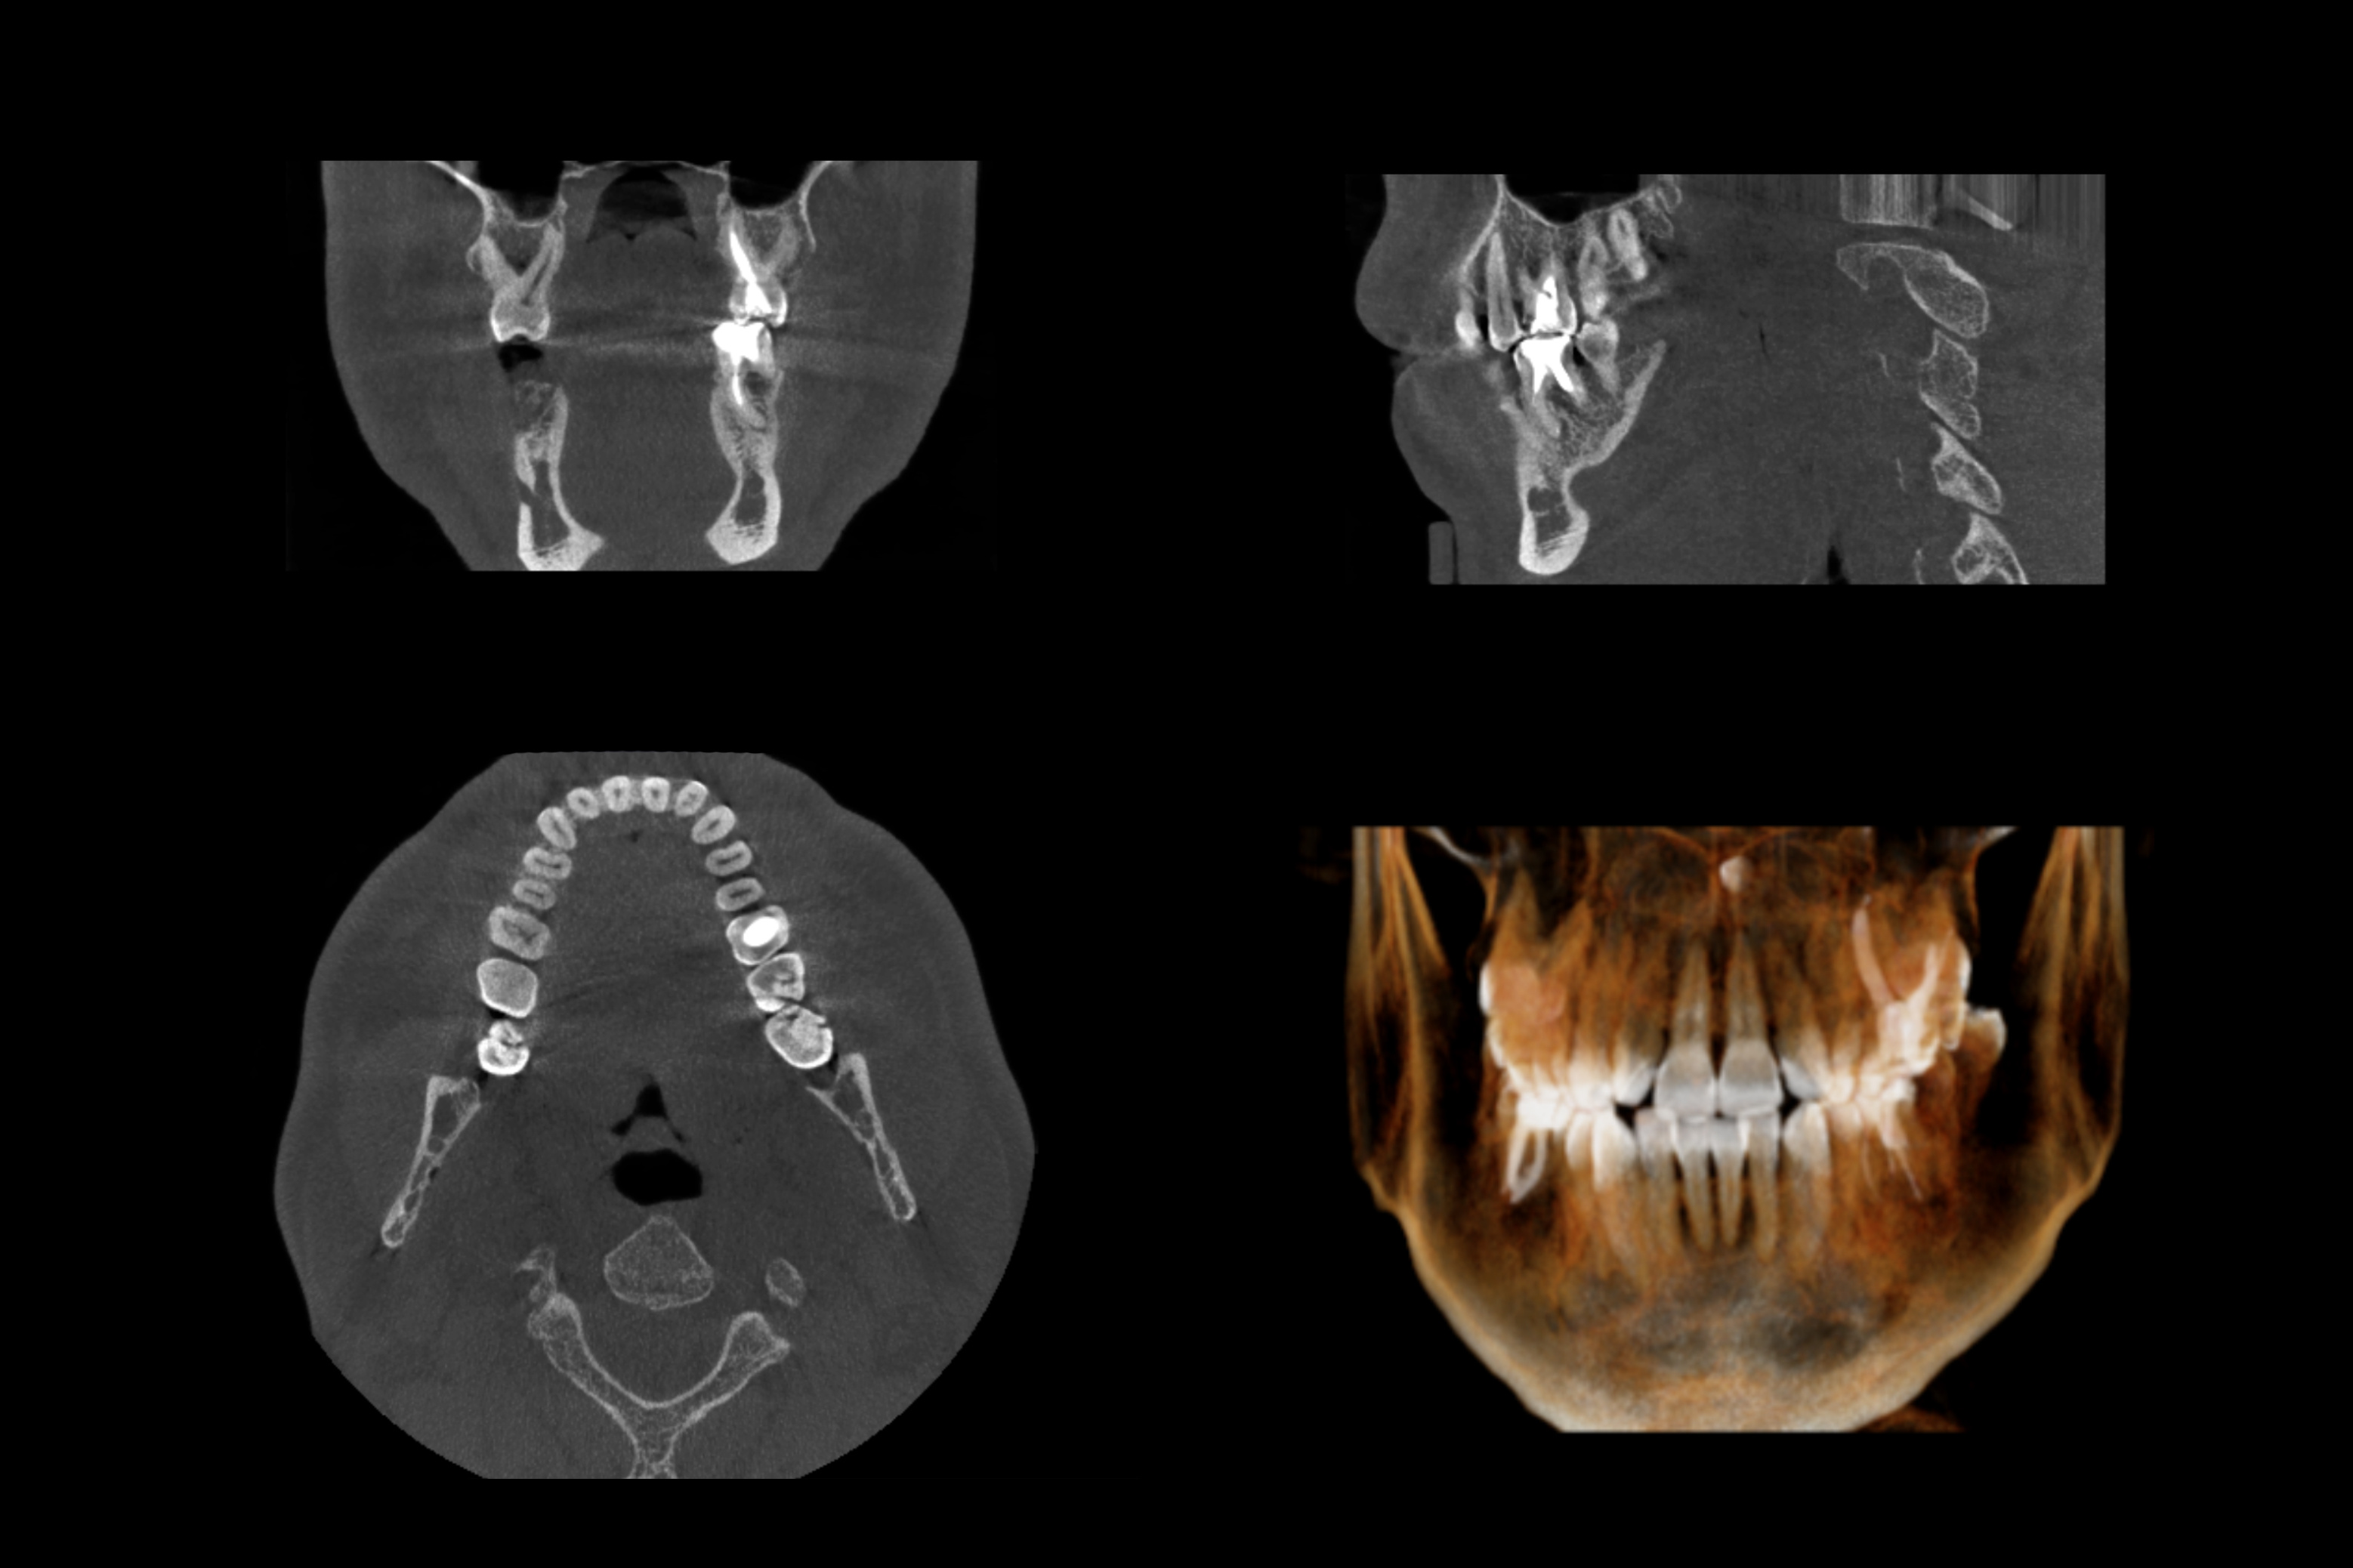

Tomografia komputerowa w stomatologii to najwyższy standard diagnostyczny. Każda dobra klinika stomatologiczna z czasem staje wobec potrzeby poszerzenia diagnostyki radiologicznej, a najlepszym rozwiązaniem jest właśnie tomografia szczęki, tomografia żuchwy lub tomografia zęba. Tylko szczególne przypadki pacjentów (podwyższonego ryzyka) wymagają wykonania tomografii komputerowej, a decyzja o jej wykonaniu jest podyktowana zasadą najwyższego bezpieczeństwa pacjenta! Sytuacje, w których badanie radiologiczne np. pantomograficzne RTG zębów ujawnia zmiany w żuchwie czy szczęce. Najszybsza weryfikacja takich zmian możliwa jest po wykonaniu tomografii komputerowej. Stomatologia już dawno przestała być niedocenianą dziedziną medycyny, a stomatolog tylko dentystą wypełniającym "dziury w zębach".

Tomografia stomatologiczna i jej zastosowanie. Tomografia zębów, Tomografia szczęki i Tomografia zęba najnowszym aparatem!

Tomografia komputerowa zębów w stomatologii znajduje zastosowanie u każdego pacjenta, ale szczególnie często jest wykonywana w następujących przypadkach:

- implanty zębów

- leczenie kanałowe w tym leczenie kanałowe pod mikroskopem

- chirurgia szczękowa

- chirurgia stomatologiczna

- ortodoncja

- periodontologia

- protetyka specjalistyczna